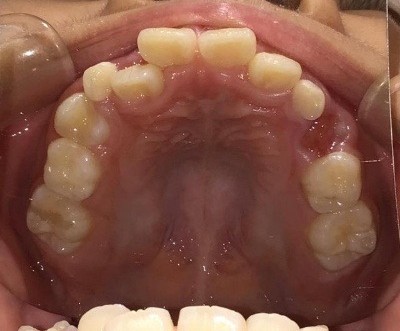

上顎

| 治療内容 | インビザライン・ファースト |

| 治療詳細 | 叢生や交叉咬合を整えるために、歯の表面にアタッチメント(白い突起)をつけました。 |

| 主訴 | 歯のがたつき 一部分だけかみ合わせが反対 |